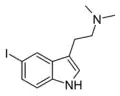

| 5-Iodo-DMT | artificial | 5-I | CH3 | CH3 | 5-iodo-N,N-dimethyltryptamine | 22120-38-3 |